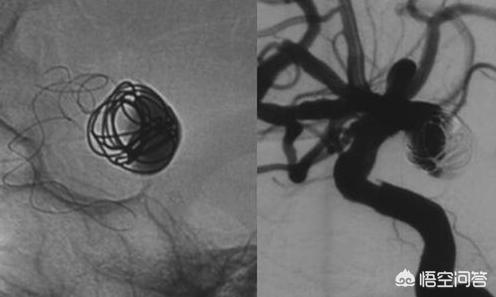

これは、冠動脈造影では心臓の血管そのものが描出されないからである。血管は軟組織であり、X線が透過してもほとんど吸収されないため、血管の画像を得ることが困難だからである。

しかし、透明な水の流れにインクを加えて見やすくするのと同じように、造影剤を用いて血液に「色をつける」(X線の取り込みを増やす)ことができる。

現在、臨床で使用されている造影剤には、主にヨード含有造影剤とロール状造影剤の2種類がある。ヨード含有造影剤は主にCT、DSA(デジタルシルエット血管造影、冠動脈造影、肝腫瘍動脈造影)などのX線画像診断に使用され、ロール状造影剤は主に磁気共鳴画像診断に使用される。